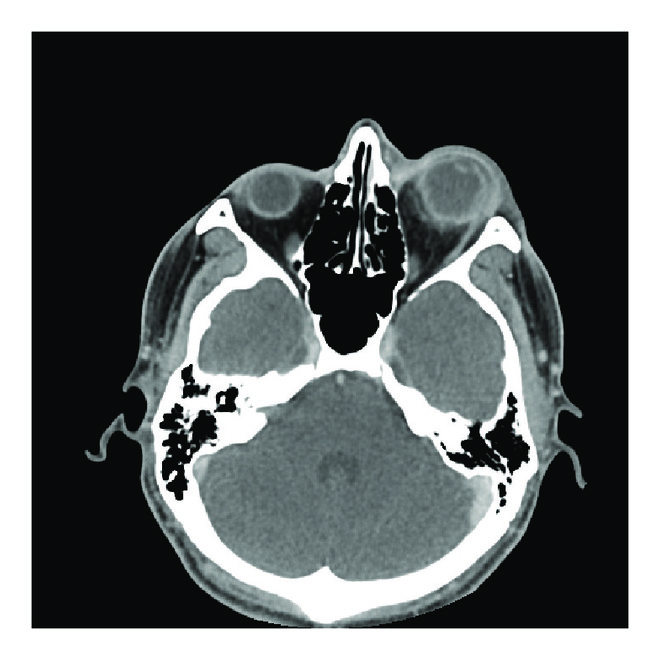

A repeat CT of the orbits identified retrobulbar fat stranding and thickening of the posterior sclera (Figure 1(b)). There was also now a focus of soft tissue density in the vitreous (Figure 1(c)). At this time consultation with a retina physician was obtained and the option of tap and inject or vitrectomy with intravitreal antibiotics was discussed. Tap and inject or vitrectomy was not performed as it was clear that this was a panophthalmitis with severe corneal melting and NLP vision.